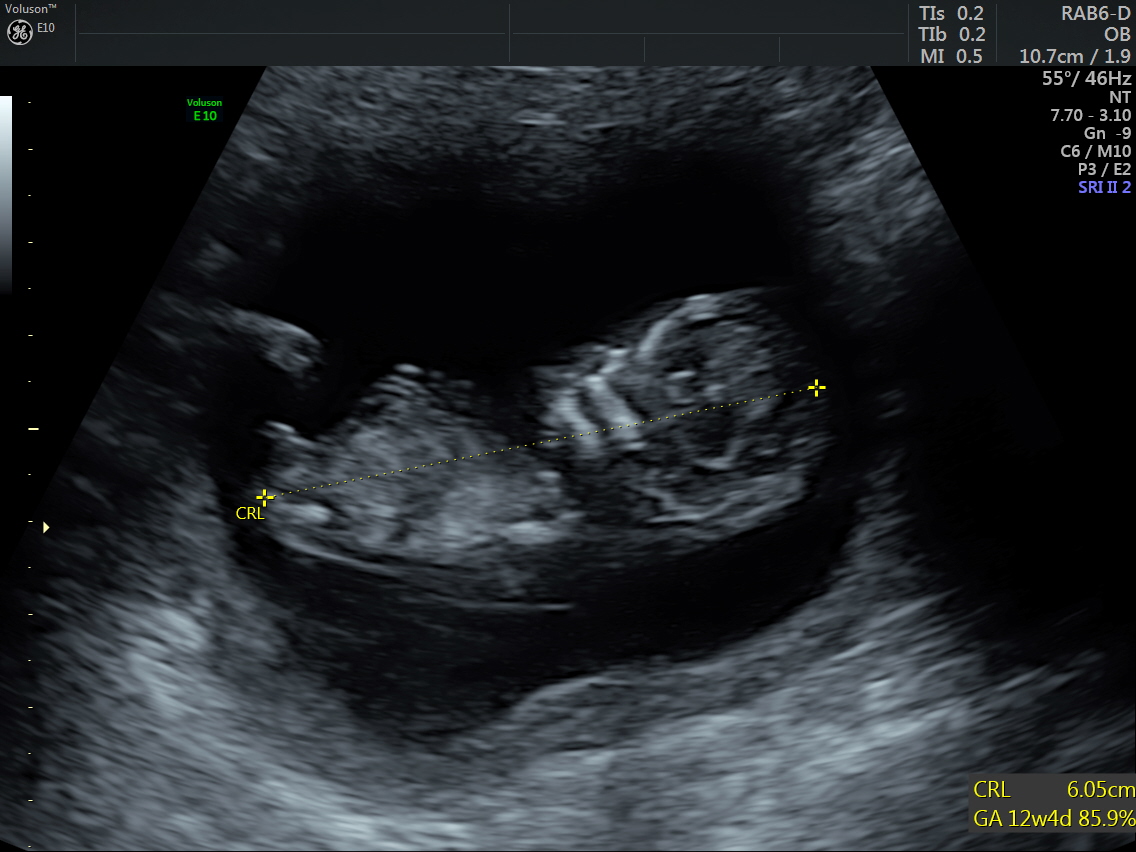

Attachment 30083Thoughts on beautiful baby #5:kissy:

I am a little over 12 weeks. Thanks for all the guesses so far!!

I'm no expert but though the nub is forked it seems to be angled. Slight boy lean ( I honestly hope I'm wrong and it turns out to be a girl).

Off the bat it looks angled and boy but shape and length look girly. I think the actual nub itself, looking closely, is girly. But I wouldn't be surprised either way.

I'm with babygirlquest, I could see this going either way - but - if you forced me to pick I'd lean girl. Keeping everything crossed that this is your girl! I remember you from years ago when we were on the sway boards for our now 2 year olds :happy:

How many weeks were you here? Hope it's girl number one but looks like maybe boy here xx

I think boy.

I honestly think it's a girl nub. What I think is that your baby's bum is angled into the air, throwing the forked nub. I think that is making it look angled from far away by when you zoom in you can see the nub is in alignment with the spine. That forking is so much more common in girl nubs and to me it looks like forking rather than stacking. The pic is a little blurry and the graininess of it makes it look more like a stacked nub but I think it's a forked girl nub. The more I think about it, the more I think girl :-)

It is actually a very funny nub pic cos when I see it from far off I think classic boy but when you zoom in I think it's classic girl! I think it's the angle of the baby that is throwing us, if your baby's spine was flat and bum angled straight or down I think it would look much more obviously girly!

So I said I wasn't going to do this, but I totally played with the pic and adjusted the angle of the spine so more flat. I know, I know...I just can't help it lol!!! I'm trying not to obsess, but I also find it fun at least and keeps my hope alive!Attachment 30155

If it was 13 weeks I'd be positive it's a girl but 12 week it's time to rise, praying it's a pink bundle for you I know exactly how you feel nubcessing hoping for a princess x

It's pretty flat because with a boy nub it would appear rised and the blop on top more round shape sticking with girl guess :)